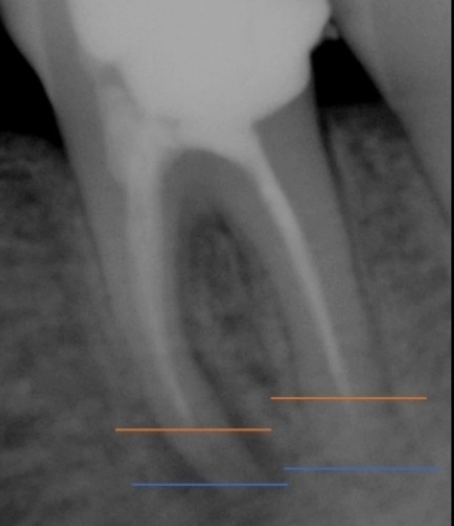

2. 근관확대 : 근관의 신경을 깨끗하게 제거하는 과정으로 신경관의 길이를 측정하게 됩니다.

4. 가압근충 : 비어있는 근관 내부를 치과재료로 채워주는 신경치료의 마지막 과정.